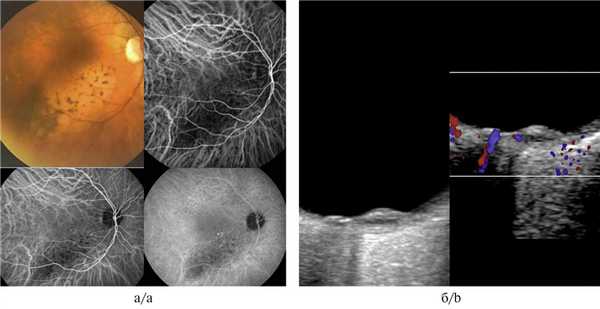

Флюоресцентная ангиография меланомы хориоидеи c неоваскулярной хориоидальной мембраной

Результаты. ОКТА у всех больных с начальной меланомой хориоидеи выявила неоваскулярную сеть под ретинальным пигментным эпителием. Диагностировали петлевидный, коленчато-извитой с неравномерным просветом гетерогенный характер сосудистой сети с многочисленными изгибами и переплетениями, расположенный под сосудами сетчатки. Ограничивающую аваскулярную зону, соответствующую склону опухоли, определили в 19 (46,3 %) из 41 случая. По периферии опухоли нашли ободок расширенных гиперрефлективных хориокапилляров. При прогрессирующем невусе хориоидеи у 39 (92,9 %) из 42 больных определили гиперрефлективные гомогенные расширенные хориокапилляры в зоне фокуса более яркого свечения по сравнению с окружающими хориокапиллярами. Аваскулярную зону в центре невуса с окружающими расширенными гиперрефлективными хориокапиллярами выявили в 3 (7,1 %) из 42 случаев. При стационарном невусе хориоидеи у всех 45 больных диагностировали гомогенные изорефлективные хориокапилляры, сходные по яркости свечения с окружающими сосудами.

Заключение. Таким образом, комплекс клинико-инструментальных методов, включающих ОКТА, дает возможность установить диагноз злокачественной опухоли сосудистой оболочки на ранних стадиях. При этом ОКТА позволяет визуализировать сосудистую сеть на уровне хориоидеи при начальной меланоме хориоидеи в 100 % случаев; отличить новообразованные опухолевые сосуды от хориокапилляров при начальной меланоме хориоидеи; предоставляет возможность установить верный диагноз и оказать своевременную помощь больным с доброкачественными и злокачественными опухолями хориоидеи.